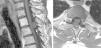

Tanto la tomografía computada (TC) como las radiografías convencionales de la columna cérvico-dorsal no mostraron hallazgos patológicos, pero la resonancia magnética (RM) de columna cérvico-dorsal evidenció un canal cervical estrecho debido a protrusiones discales múltiples y extrusión discal con compromiso neuroforaminal C6-C7 derecho. Incidentalmente se observó una imagen de bordes netos y aspecto quístico, con alta intensidad de señal en ponderación T2 y baja intensidad de señal en ponderación T1, sin realce tras la administración de gadolinio. Esta se localizaba a la altura del espacio intersomático D1-D2, en relación dorsal a la médula espinal (figs. 1–3).